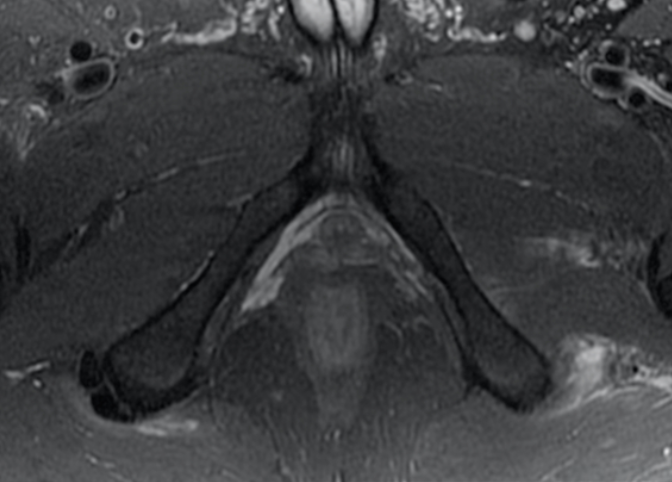

A 66-year-old male with right anterior elbow pain, ecchymosis, and a “lump” in his right upper extremity after a ground level fall.